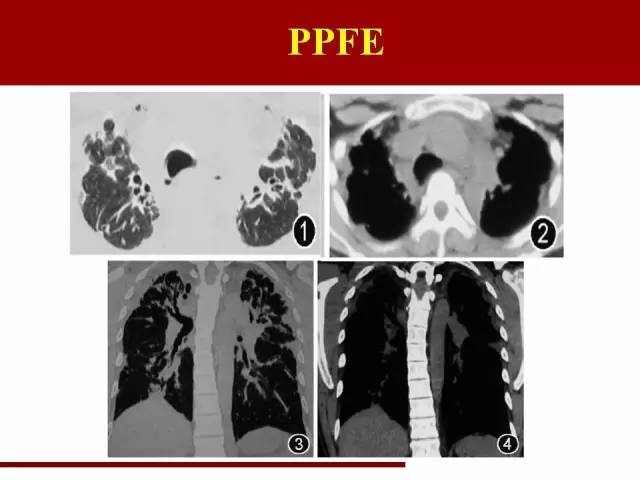

胸膜肺弹力纤维增生症PPFE

最后一类是一个年轻的间质性肺炎,2004年命名的,所以在2002年那一版分类里面没有这一类

PPFE近些年也逐渐被重视,报道逐渐增多

PPFE在间质性肺炎里面两个唯一:唯一主要同时累及肺和胸膜的间质性肺炎,唯一倾向中上肺野分布的间质性肺炎

中上肺野肺纤维化伴胸膜增厚,容积缩小

需要与尘肺,特别是石棉肺鉴别

主要鉴别点在于石棉肺的胸膜斑更明显,并且伴有钙化